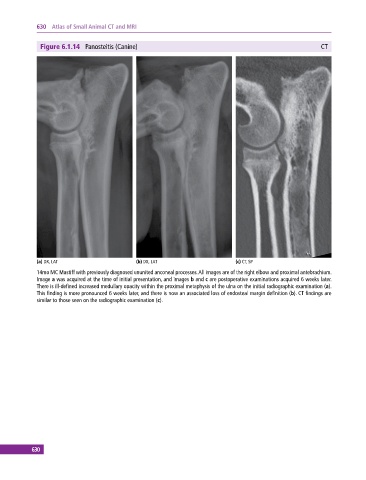

Figure 6.1.14 Panosteitis (Canine) CT

(a) DX, LAT (b) DX, LAT (c) CT, SP

14mo MC Mastiff with previously diagnosed ununited anconeal processes. All images are of the right elbow and proximal antebrachium.

Image a was acquired at the time of initial presentation, and images b and c are postoperative examinations acquired 6 weeks later.

There is ill‐defined increased medullary opacity within the proximal metaphysis of the ulna on the initial radiographic examination (a).

This finding is more pronounced 6 weeks later, and there is now an associated loss of endosteal margin definition (b). CT findings are

similar to those seen on the radiographic examination (c).